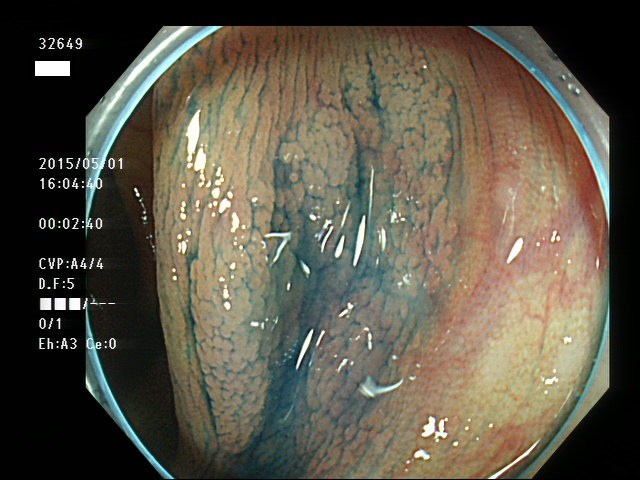

上記100名より抽出した平坦・陥凹型腺腫(=癌化の危険が高いが見落としやすい病変)の内視鏡写真